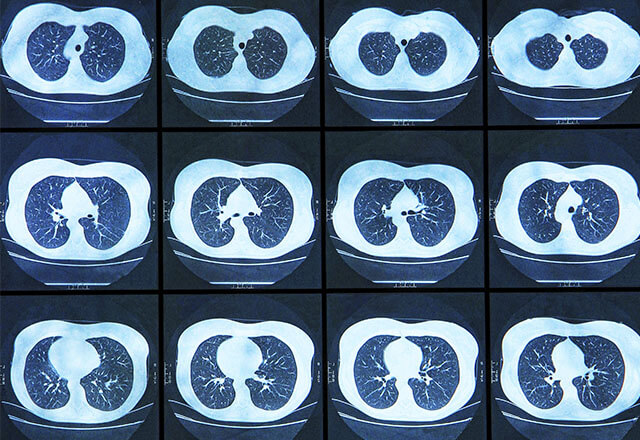

• 電腦掃描可發現腫瘤和大致區分其良、惡性,準確率較高,比肺部X光更能準確檢測到初期及較細小的腫瘤

• 低劑量胸腔電腦斷層掃描(LDCT):LDCT 以 X 光技術穿透人體,然後以電腦影像從不同角度檢視肺部,由於其使用的輻射量較低,因此常用於進行肺癌篩檢